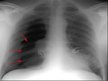

2. Eksudatīvā stadija- novēro 12-72h pēc sākuma. Endotēlijs kapilāros un alveolocīti tiek bojāti. Attīstās plašs iekaisīgs process ar Neu un Ly migrāciju. I un II tipa alveolocīti iet bojā, seko surfaktanta deficīts un tam sekojošs alveolu kollapss. Ieceļojušie proteīni saistās ar bojāto šūnu paliekām un veido hialīnās membrānas. Alveolas pildītas ar transudātu. Klīniski attīstās un progresē hipoksēmija. Plaušu rentgenogrammā redz difūzu, bilaterālu, heterogēnu aizēnojumu (~ plaušu tūskai). Citas laboratorās analīzes nespecifiskas, galvenokārt norāda uz pamatslimību. Ilgst aptuveni 7 dienas.